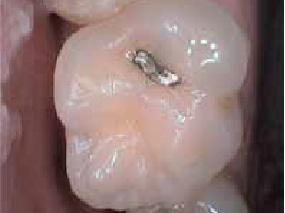

by Larry M. Guzzardo

The process of moving a patient from one member of the team to another is called a “hand-off.” We do this by never leaving a patient alone without letting them know who and what to expect next. It means you never leave them alone in a treatment room, wondering who’ll come in next or how long they will be there, or you never drop them off at the front desk to talk to a receptionist on the phone. It requires informing your patient of each step of the way by explaining who and what comes next, anticipating their needs, and introducing them to the next team member, all while creating an environment that will increase treatment acceptance and reduce canceled and broken appointments.

This is what should happen to help patients “connect the dots”: The dentist should be communicating with the patient throughout the appointment about what they are doing, why they are doing it, and how things are progressing. At the end of the appointment, as the chair is brought up, the dentist must take command by coming around to the front of the chair, connect with the patient by making eye-to-eye contact, and take the following 10 steps:

1. Outline exactly what treatment the patient received, including the number of teeth restored, the number of surfaces, and the depths and severities of every tooth restored, in lay terms with no jargon.

2. Let the patient know what he or she should expect to feel following the appointment, including any possible discomfort and the reasons why.

3. Communicate a clear message of exactly

what the patient is having done at the next appointment. This is not meant to be a laundry list; rather, it should cover exactly which teeth will be addressed next time and the reasons why.